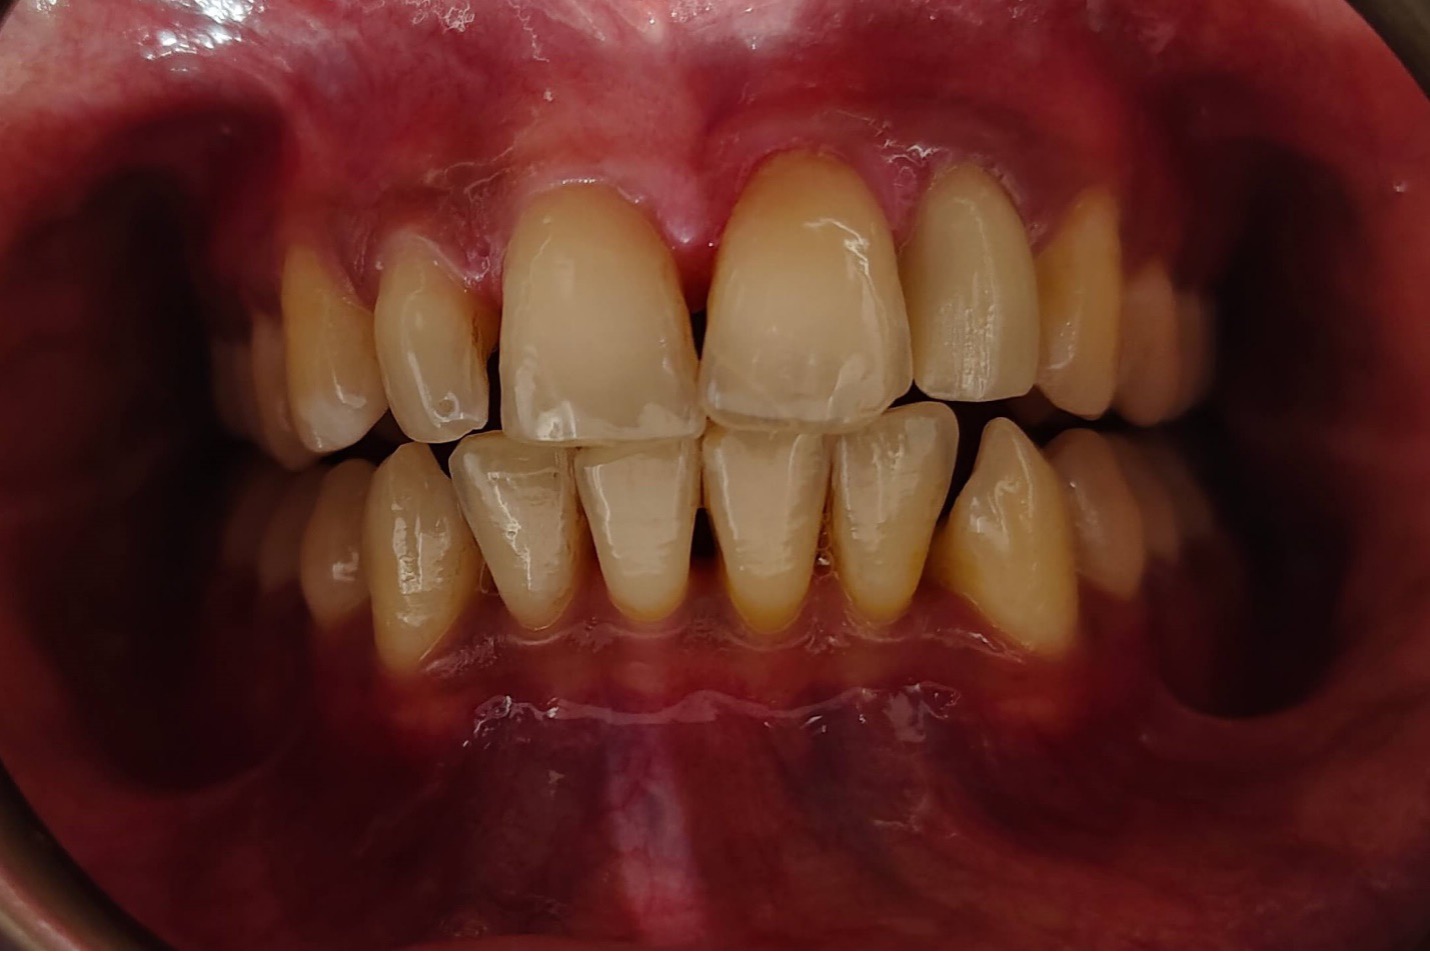

Zirconia, and E-max are the best crowns and bride choice for front/anterior teeth all across the world because their shades perfectly matches the natural teeth shades. Porcelain fused to metal (PFM) is not recommended on front teeth because of the metal hue and gray gum margins as discussed above.

On the other hand, the selection of crown and bridge of back or posterior teeth crown is totally dependent on tooth condition (weak or solid), budget of the patient, mastication (biting forces), position of the tooth required crown e.g., upper back or lower back tooth and patient preference. Usually, Zirconia high strength, PFM and metal crowns are recommended for back teeth.

Always take advice and follow the selection of crown material for buckteeth because your dentist knows the tooth structure condition better than you.